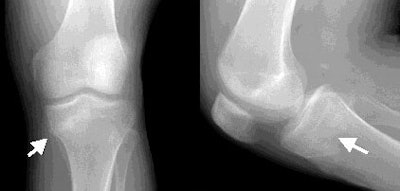

Radiographic examination demonstrated a linear region of sclerosis in the left proximal metaphyseal tibia in the approximate region of the physeal scar. Additionally, there was a slight varus deformity of the proximal medial tibia, and bowing of the medial metaphyseal cortex.

| Radiographs demonstrate a linear region of sclerosis in the metaphyseal region of the physeal scar (white arrows). There is also slight bowing of the medial mediphyseal cortex (left image). |